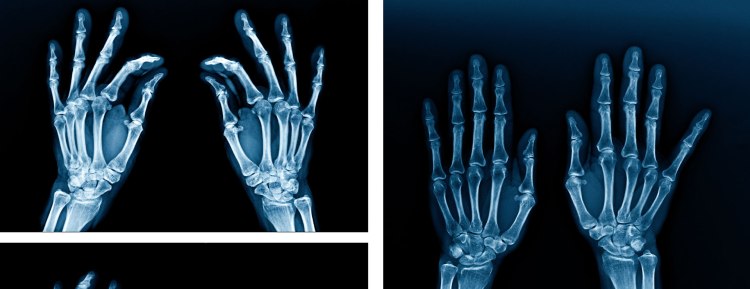

El proceso físico para la radiografía digital es en realidad similar a las radiografías dentales tradicionales que usan película: con la radiografía digital, su dentista inserta un sensor en su boca para capturar imágenes de sus dientes, pero ahí es donde se encuentran las similitudes entre la radiografía dental convencional y la digital. terminan los rayos. Aunque se parece a la película que se usa para las mordidas y otras radiografías, el sensor digital es electrónico y está conectado a una computadora. Una vez que se toma la radiografía, la imagen se proyecta en una pantalla para que la vea su dentista.

Imágenes de mayor calidad: el tamaño estándar de las radiografías tradicionales puede dificultar la visualización, pero la radiografía digital ha acabado con la mentalidad de talla única Una vez en la pantalla, las radiografías digitales se pueden ampliar o magnificar para una mejor visualización de la estructura del diente. El brillo, el contraste y el color también se pueden ajustar, lo que le permite a su dentista ver las caries pequeñas más fácilmente. Si necesita una copia impresa de su radiografía, también se pueden imprimir imágenes digitales.